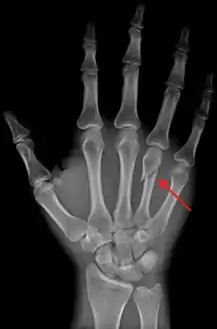

كسر الملاكم هو الاسم الشائع لكسر في عنق العظام التي تشكل براجم اليد.[1][2][3] يحدث الكسر عادة في عنق العظم السنعي الخامس، الذي يشكل برجمة خنصر ولكن نفس الاسم يمكن أن يستعمل لكسر يحدث في أي من الأسناع. تعرف هذه الأذية أيضاً بكسر المتشاجر ; يمكن أن يسمى كسر في عنق السنع الرابع أو الخامس بكسر الحانة.

![]() DP (PA) right hand x-ray showing fracture at the neck of العظم السنعي الرابع DP (PA) right hand x-ray showing fracture at the neck of العظم السنعي الرابع | |